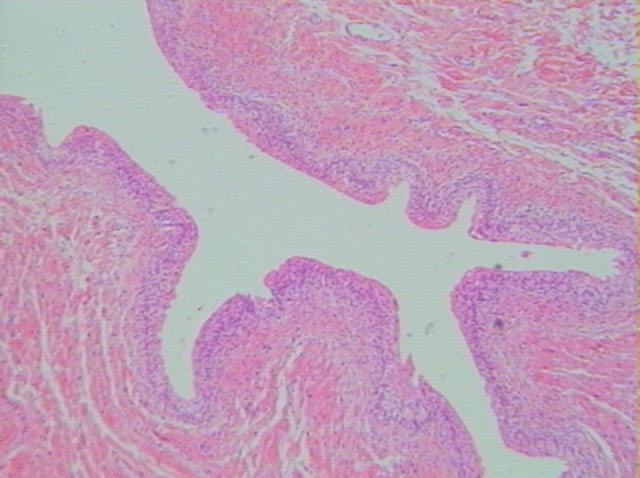

平滑肌層

結締組織

移形上皮

膀胱空腔

切片位置:膀胱(urinary baldder)

切片倍率:40x

染色方式:h&e stain

低倍放大(40x)之膀胱,當膀胱儲存之尿液排空而呈鬆弛狀態時,其管壁向腔內凸入形成皺褶;但隨著儲存尿液容積之增加,其管壁皺褶也隨容積增加時表面積之擴張而逐漸被撐平。其內層由移形上皮所覆蓋,上皮下方為結締組織。結締組織在內層緊鄰上皮部分為緻密不規則之結締組織,在結締組織內含多量之彈性纖維,而較外層靠近平滑肌肌肉層部份則為疏鬆結締組織。